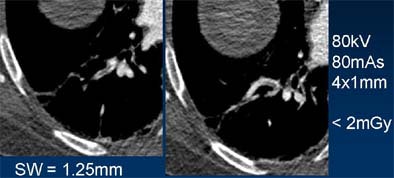

| Lower pitch (left) can be used to reduce artifacts in thin-section imaging, an approach that is particularly useful in the peripheral skeleton or in the C-spine, above. Images courtesy of Dr. Mathias Prokop. |